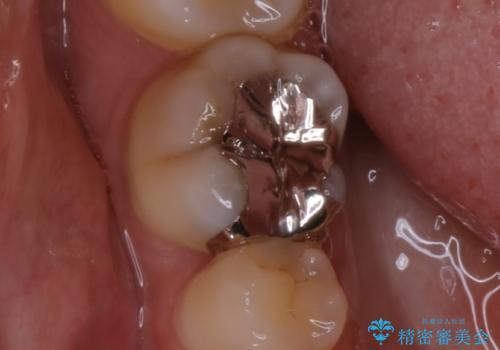

- 銀歯のやり替えをご希望された患者様です。手前の歯にもプラスチックと歯の間に虫歯が出来ていたため、両方とも適合の良いセラミックで補綴しました。

適合不良の補綴物は二次的な虫歯発生のリスクが高まります。

自費診療で用いられる材料は保険適応の材料に比べて、より精密で適合の良い被せ物作ることができるため、長期的な虫歯のリスクを大幅に減らすことが可能です。